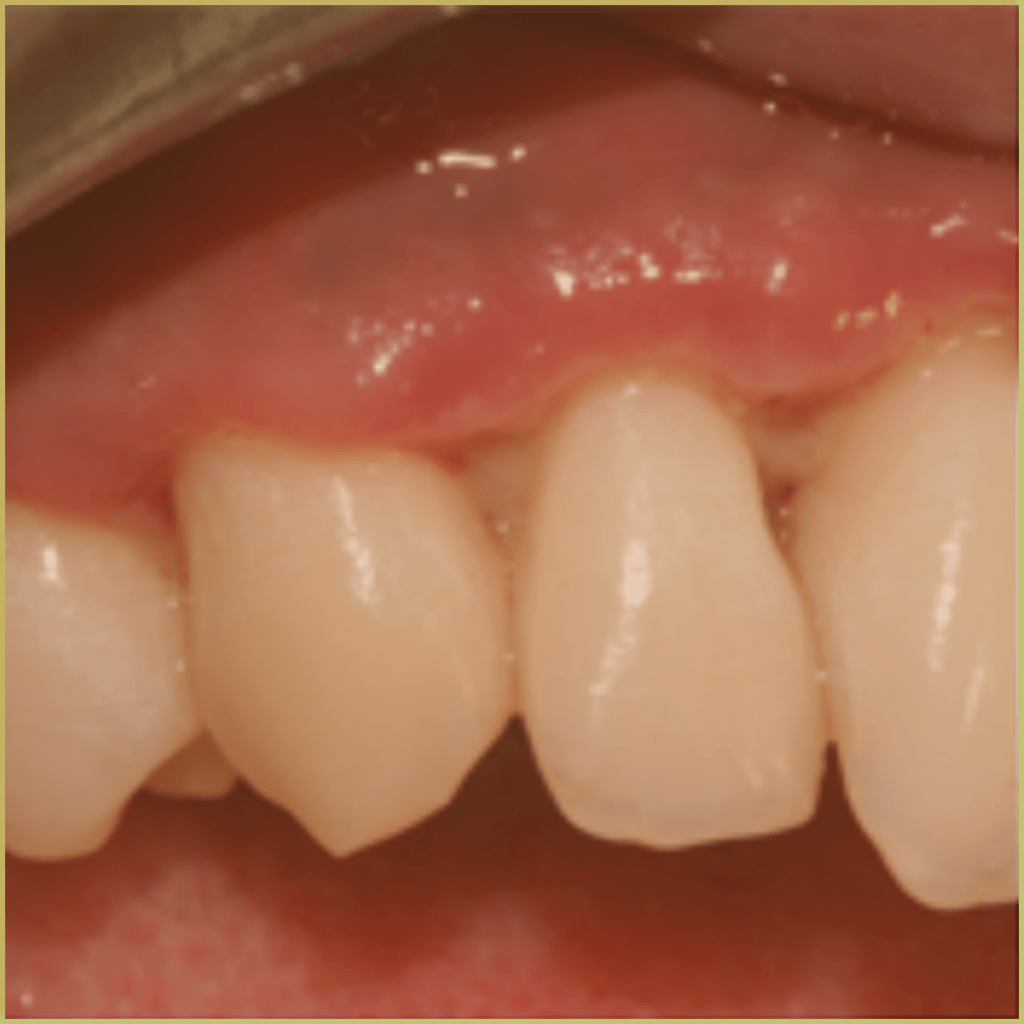

ANUG

Acute Necrotizing Ulcerative Gingivitis (ANUG, Vincent’s disease, trench-mouth) is a relatively rare non-communicable microbial disease caused by Fusobacterium nucleatum, Borrelia vincentii, and other bacterial species including Prevotella. If left untreated, ANUG can progress to cause rapid tissue destruction and/or necrotizing ulcerative periodontitis (NUP). Risk factors for ANUG include an impaired host immune response, poor oral hygiene, nutritional deficiencies, intense smoking, and psychological stress. The common clinical presentation includes:

- Edematous and blunted (“punched-out”) interdental papillae with crateriform necrosis.

- Pain, regional lymphadenopathy, fetor oris (bad breath), fever, and malaise.

- Ulcerated areas are covered with a grayish pseudomembrane.

- Gingiva bleeds easily.

Diagnosis is usually based on the lesion history and clinical presentation only. Your differential diagnosis should include:

- Leukemia or other Immunosuppression-related condition.

- Other infections (herpetic gingivostomatitis).

- Vesiculobullous diseases (mucous membrane pemphigoid, erosive/bullous lichen planus, pemphigus vulgaris, paraneoplastic pemphigus).

Treatment options include:

- Identification and elimination of predisposing factor(s).

- Local debridement and ultrasonic scaling.

- Instructions related to oral hygiene (at home care).

- Topical chlorhexidine or povidone-iodine.

- Systemic antibiotics (tetracycline, metronidazole).